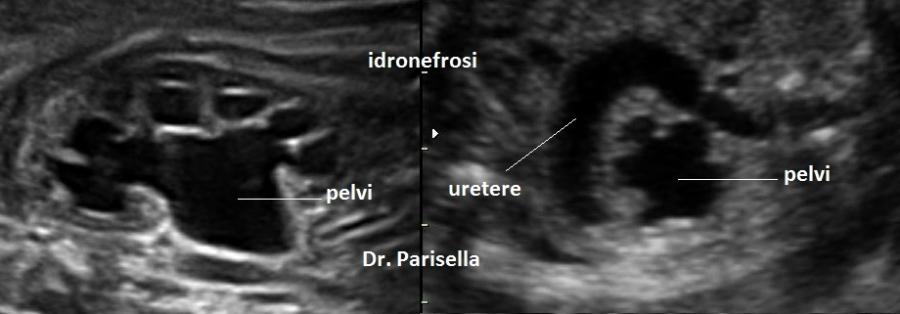

SCD1 : o Sindrome di Jarcho-Levin è trasmessa con carattere autosomico recessivo ed è dovuta a mutazione del gene DLL3. E' caratterizzata da anomalie vertebrali (emivertebre, fusione di vertebre….), anomalie di numero e di forma delle coste, grave scoliosi, malallineamento delle vertebre cervicali e delle coste anche in epoca precoce,  aspetto “a granchio” della gabbia toracica dovuto posteriormente alla fusione delle coste ed anteriormente alla loro divaricazione; si associano ernia diaframmatica e polidattilia postassiale.  NT aumentata nel I trimestre. Si possono inoltre associare, meno frequentemente (15-30%): microcefalia, palatoschisi, sindattilia, campodattilia, spina bifida occulta, difetti della parete addominale, difetti anali, idrocefalia, idroureteronefrosi, cardiopatia.